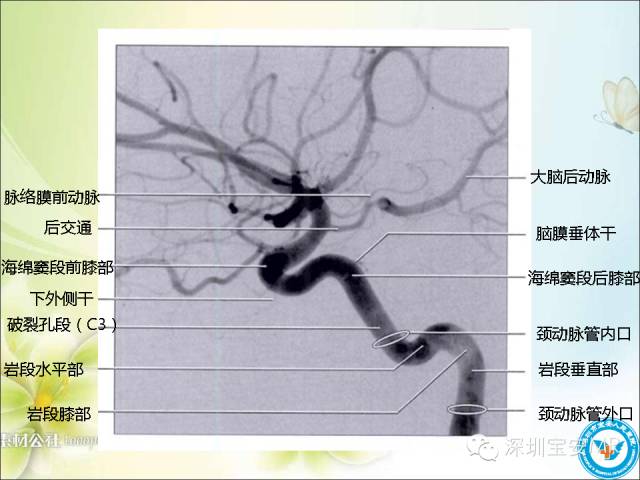

【PPT】颈内动脉颅内段影像解剖(附临床血管病例)